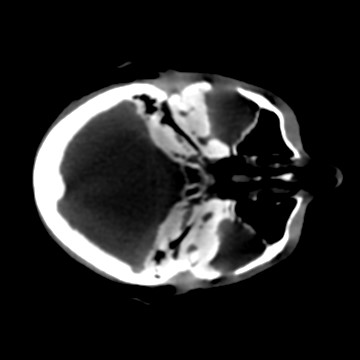

Cone-beam CT (CBCT) employs a flat-panel detector to achieve three-dimensional imaging with high spatial resolution. However, CBCT is susceptible to scatter during data acquisition, which introduces CT value bias and reduced tissue contrast in the reconstructed images, ultimately degrading diagnostic accuracy. To address this issue, we propose a deep learning-based scatter artifact correction method inspired by physical prior knowledge. Leveraging the fact that the observed point scatter probability density distribution exhibits rotational symmetry in the projection domain. The method uses Gaussian Radial Basis Functions (RBF) to model the point scatter function and embeds it into the Kolmogorov-Arnold Networks (KAN) layer, which provides efficient nonlinear mapping capabilities for learning high-dimensional scatter features. By incorporating the physical characteristics of the scattered photon distribution together with the complex function mapping capacity of KAN, the model improves its ability to accurately represent scatter. The effectiveness of the method is validated through both synthetic and real-scan experiments. Experimental results show that the model can effectively correct the scatter artifacts in the reconstructed images and is superior to the current methods in terms of quantitative metrics.